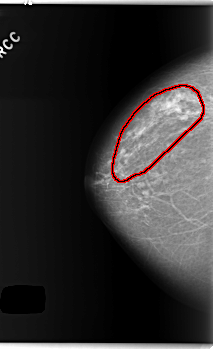

C_0254_1.RIGHT_CC

RIGHT_CC LINES 5928 PIXELS_PER_LINE 3608 BITS_PER_PIXEL 12 RESOLUTION 50 OVERLAY

FILE: C_0254_1.RIGHT_CC.OVERLAY

TOTAL_ABNORMALITIES 1

ABNORMALITY 1

LESION_TYPE CALCIFICATION TYPE AMORPHOUS DISTRIBUTION REGIONAL

ASSESSMENT 4

SUBTLETY 2

PATHOLOGY BENIGN

TOTAL_OUTLINES 1